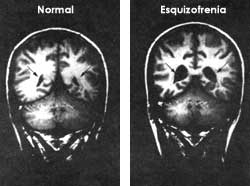

Imagen tomada de: https://bibliotecadigital.ilce.edu.mx/sites/ciencia/volumen3/ciencia3/158/html/sec_8.html [21 Noviembre 2014]